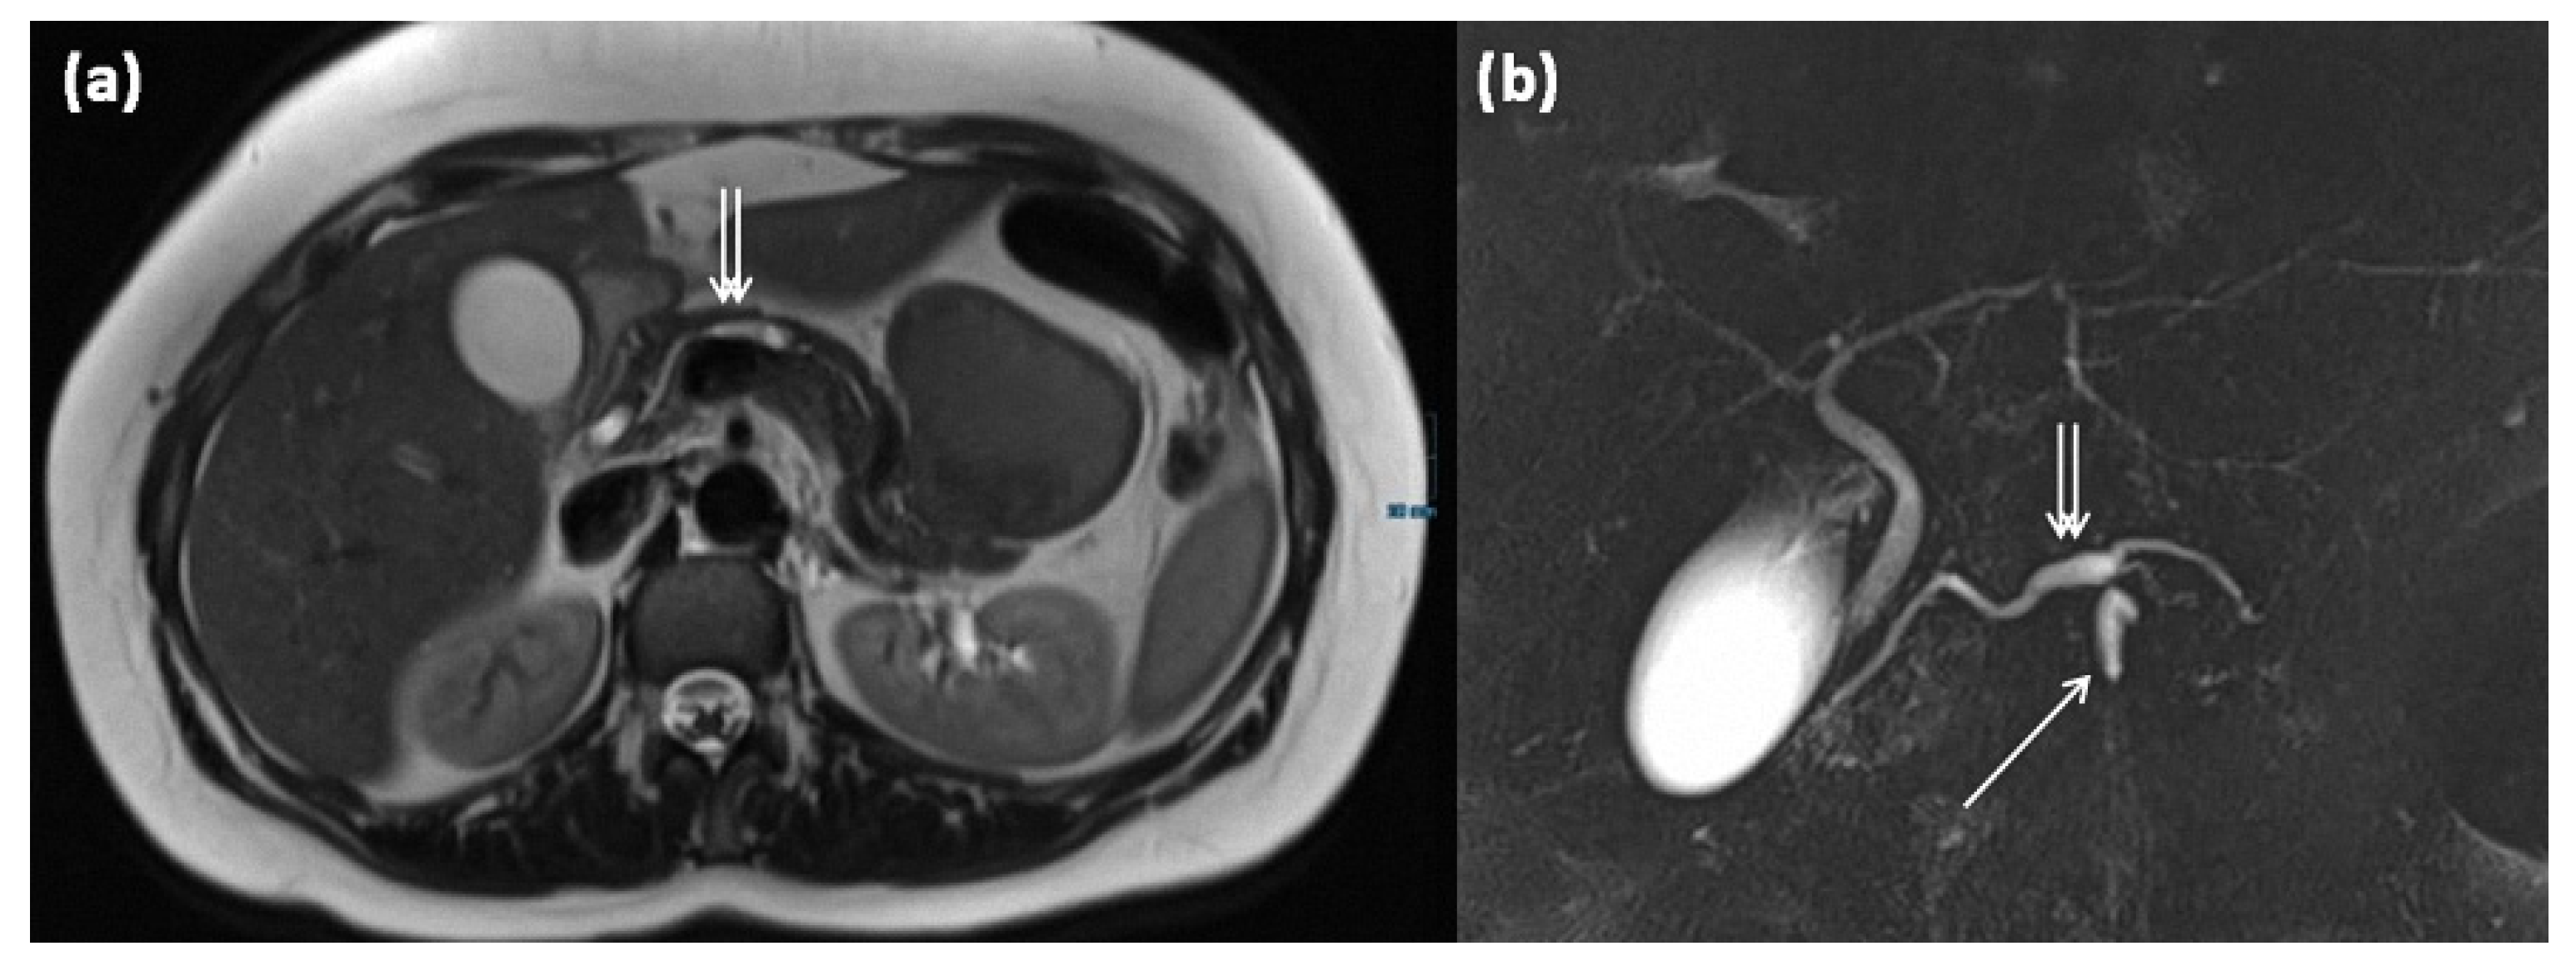

3.5.1. Main Duct IPMN